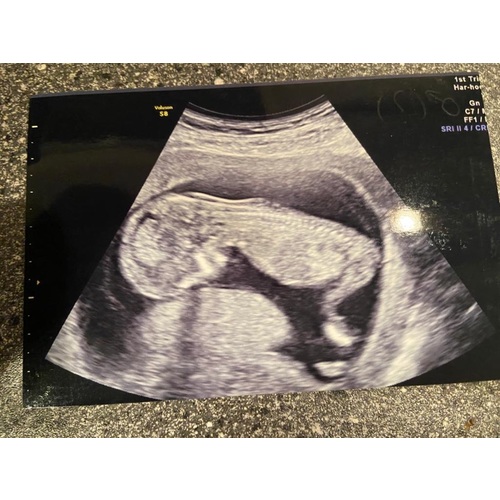

Ik heb hetzelfde..dit is mijn echo..mijn gevoel zegt nog steeds dat ze er naast zitten

5 jaar geleden

Hoi met 15 weken heb ik een echo gehad. Daarop dacht de VK een meisje te zien maar moest de 20 wkn echo ook afwachten. Hier een foto van de echo. Is onderkant van de billen en benen. Denk ook dat het een meisje is want met 15 wkn zou je toch al iets van balzak en piemeltje moeten zien. Hier mijn echo foto. Wat denken jullie?